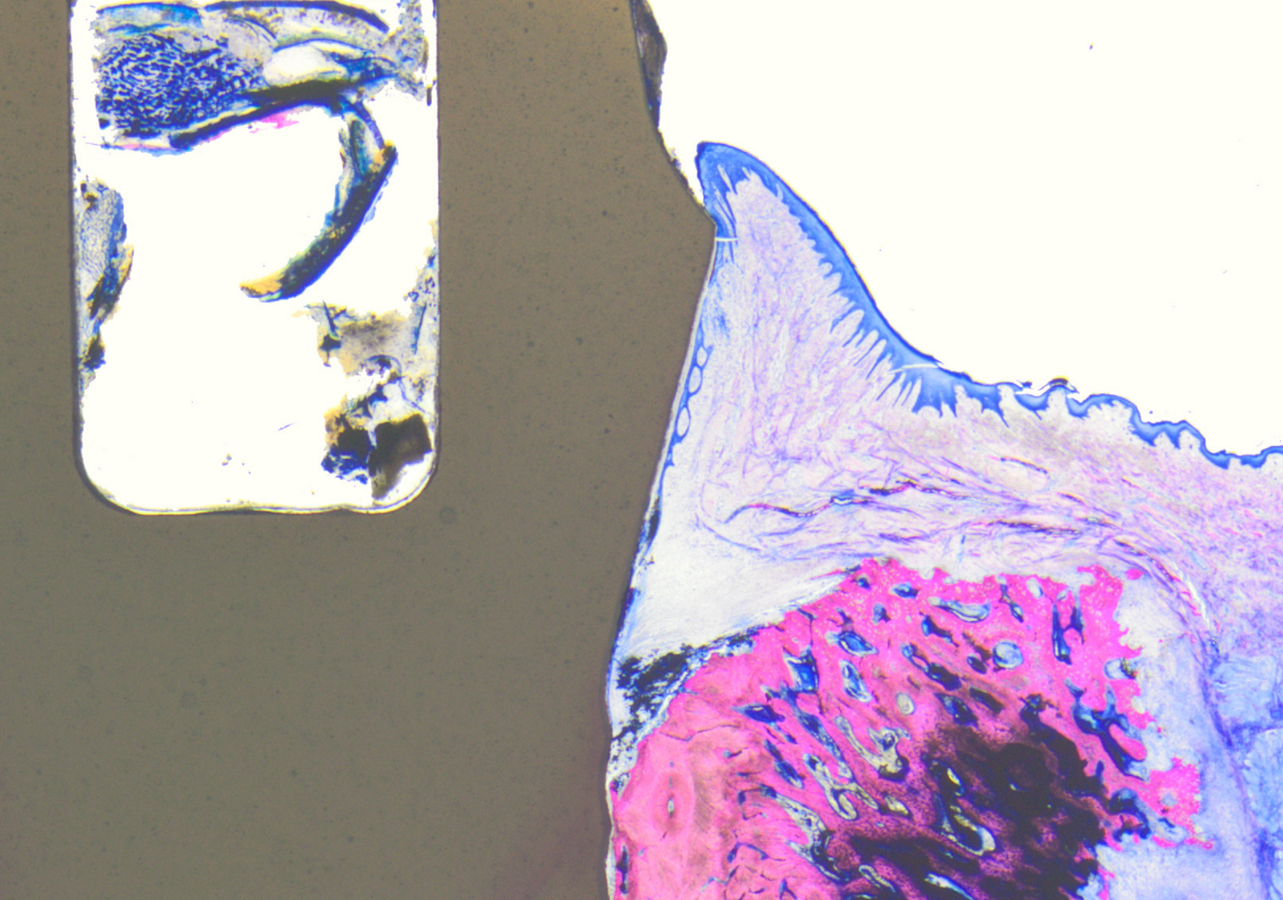

O sistema de implantes dentários Patent demonstrou uma ligação entre a mucosa peri-implantar e uma superfície sintética — uma inovação na história da odontologia. Uma equipe de pesquisa liderada pelo Prof. Anton Sculean, Dr. Peter Schüpbach , Dr. Roland Glauser e Prof. Dieter Bosshardt confirmou essa nova ligação celular biomecânica em estudos histológicos.

Histologia de um implante patenteado (esquerda) quatro semanas após a inserção; graças à adesão do tecido mole à superfície transmucosa do implante (círculo vermelho), nenhuma placa é visível abaixo do nível do tecido mole. (Imagem: Dr. Peter Schüpbach)

Os implantes Patent passam por um tratamento de superfície patenteado que confere propriedades mucofílicas e oclusivas de células — melhorando a integração com os tecidos moles e criando uma barreira à entrada de bactérias —, além de uma topografia de superfície modelada na estrutura natural do dente. Como resultado, as células epiteliais começam a crescer na superfície transmucosa do Patent já nos estágios iniciais da cicatrização, estabelecendo uma ligação com ela.

No EuroPerio11, em Viena, Áustria, onde esses resultados histológicos foram apresentados durante um simpósio, o Dr. Glauser enfatizou que a ligação do tecido mole à superfície transmucosa da Patente funciona como uma barreira protetora dinâmica que impede a migração da placa para o tecido, protegendo-o, assim, da invasão bacteriana. Consequentemente, o risco de inflamação e recessão tecidual é bastante reduzido, a progressão da mucosite para a peri-implantite é prevenida e a estética estável é mantida a longo prazo.